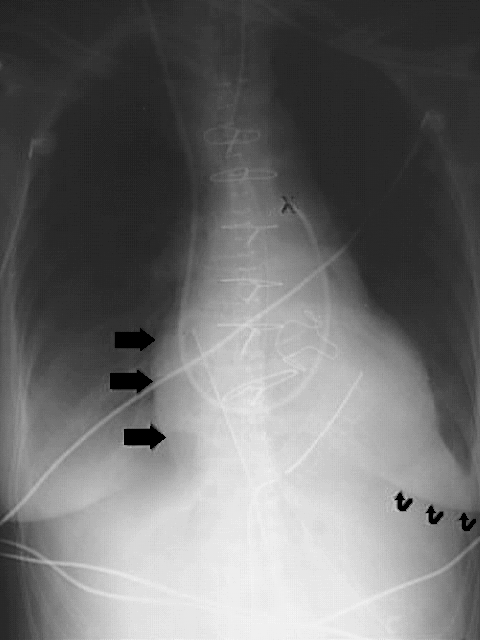

Thorax - Chest Valves and Catheter